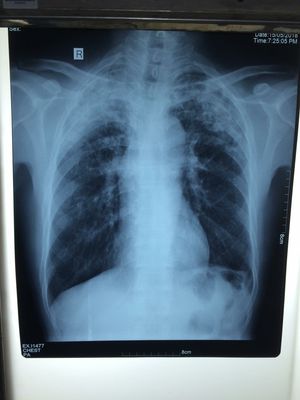

case report from Pneumo Department KSFH, Patient 50 years old (Male) Cc: Dyspnea associate with chronic productive cough and oppression thoracic. Past history: -Non previous anti-TB treatment -Non TB disease -Primary smoking 25 packing per year -DM and HTN Unknown PE report -Crackle sound bilateral on upper lobe -Tachycardia -Hemodynamic stable -Dyspnea type polypnea RR >26 with SpO2: 92% air environmental -Other system normal Questions 1. Depend on imageries include CxR, ECG and Clinical symptoms and PE. what's your 1st Dx...? 2. Next step to confirm Dx base on CxR link to your clinical Dx....? 3. Management process...? 4. If condition not improve, alteration on GA and Perisistent fever. Next step to do....? 5. If condition of patient developing to severe sepsis. What's your essential process and best way to solve Pt....? 6. Which of Bilan do you need to evaluation and observes evolution of the disease....? 7. Indication of Bilan control....?

1. Susp. TB, 2. Sputum tes 3. Nebulizer with short beta2agonis, 4. Intravenous fluid with Nacl 0,9%+Aminofilin drip, 5. Antibiotik injection such as ceftriaxone, 6. ? 7. ?

1. Susp TB, especially if there is any TB’s pulmo and systematic symptoms. 2. Sputum BTA, take tuberculin test in children can be helpful than sputum test. 3. O2, Nebu, ambroxol 4. Wide spectrum Antibiotics to prevent sepsis anf if the px not improve 5.&6. Its hard to decide any management if havent see the condition directly